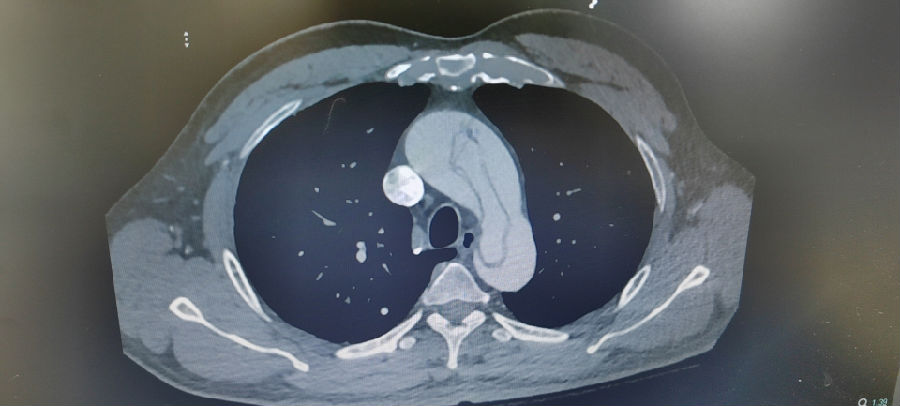

病人至急诊就诊,一旦急诊心脏超声、主动脉CT提示主动脉夹层,并存在血性心包积液,那么,该患者的术前准备紧凑性及进入手术室手术的画面,可能会是“x2.0”甚至更高倍数的播放速度。

主动脉夹层(未切开)

术后复查CT